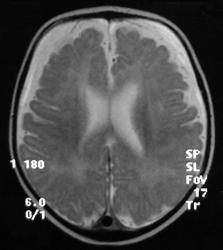

МРТ головного мозга

• Выраженное расширение субарахноидального пространства над лобными долями, обусловленное уменьшением объема лобных долей;

• Атрофия белого вещества;

• Изменение паттерна извилин: Имеются участки, где четко видны мелкие извилины, их количество увеличено по сравнению с нормальным. На других участках, напротив, извилины плоские, широкие;

• Граница между белым и серым веществом четко не дифференцируется;

• Сильвиева щель расширена, больше слева;

• Отчетливо выявляется зияние островка, что говорит о том, что височная доля не сформирована;

• Определяются зоны гиперинтенсивного сигнала в субинсулярных отделах;

• Желудочки расширены.

• Атрофия лобных долей;

• Смешанная гидроцефалия;

• Признаки нарушения формирования борозд лобных долей и перисильварного региона;

• Симметричная двусторонняя передняя перисильварная полимикрогирия;

• Атрофия (гипогенезия) мозолистого тела.